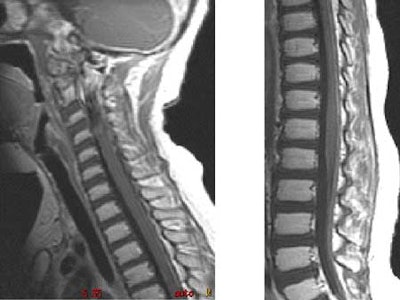

The Duke team sought to answer these questions by retrospectively reviewing the clinical records and imaging studies of 8 patients with TRB over 15 years. They looked for the presence of leptomeningeal tumor, the time of discovery of an intracranial mass, and the interval from discovery of intraspinal leptomeningeal disease. All 8 patients had cranial MR imaging, and 6 had spinal MR imaging using standard protocols.

Over the course of the study, six patients developed intracranial metastases as seen on MR imaging. Five of the patients developed intraspinal metastases, with four seen on MR, and one diagnosed by lumbar puncture, Provenzale said.

The time from detection of the primary intracranial mass and discovery of the intracranial leptomeningeal disease ranged from 7-26 months (mean, 13 months). Most were diagnosed within a year, however. The mean interval to discovery of intraspinal metastases was 9 months, with a range of 0-26 months.

A discernible progression pattern was seen in about half of the patients, who were diagnosed and treated for intracranial disease with some combination of chemotherapy, radiation, and surgery, Provenzale said. Following treatment, the primary intracranial tumor shrank, and there was a period of quiescence lasting from 1-4 years, followed by rapid development of intracranial and intraspinal leptomeningeal metastases.

"At some point in their therapy, many of our cases had little or no residual pineal tumor at the time of discovery of intracranial or intraspinal tumor spread, so if you're looking to see where disease is going to spread in these patients, it's equally important to look at the leptomeningeal spaces as it is to look at the site of the intracranial mass, whether it be pineal or suprasellar," Provenzale said.

Finally, because spinal metastases were present in some cases at the time of discovery of an intracranial mass, Provenzale recommended that spinal imaging be performed at the time of diagnosis of the primary tumor.

"Our protocol based on this data is to perform brain and spine MR imaging at the time of diagnosis of the intracranial tumor, and then at two-month intervals in the first year, four-month intervals in the second year, and at six-month intervals thereafter.... This seems to be a very aggressive neoplasm," he said.